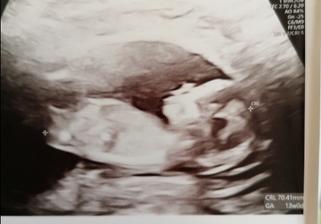

Nase vysnivane <3

Snazili sme sa pol roka,a je to tu - NAS KRASNY ZAZRAK <3